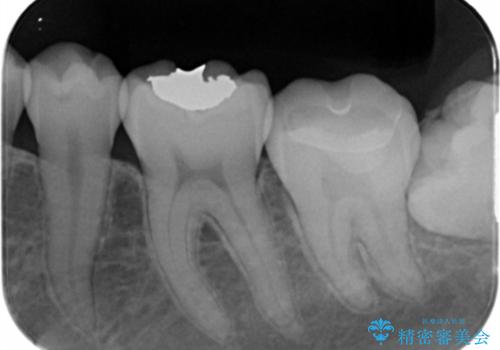

- 矯正を考えている患者様です。

歯の噛む面(咬合面)に虫歯が見られたので拡大鏡下で除去し

白い詰め物(e-maxインレー)にて治療しました。